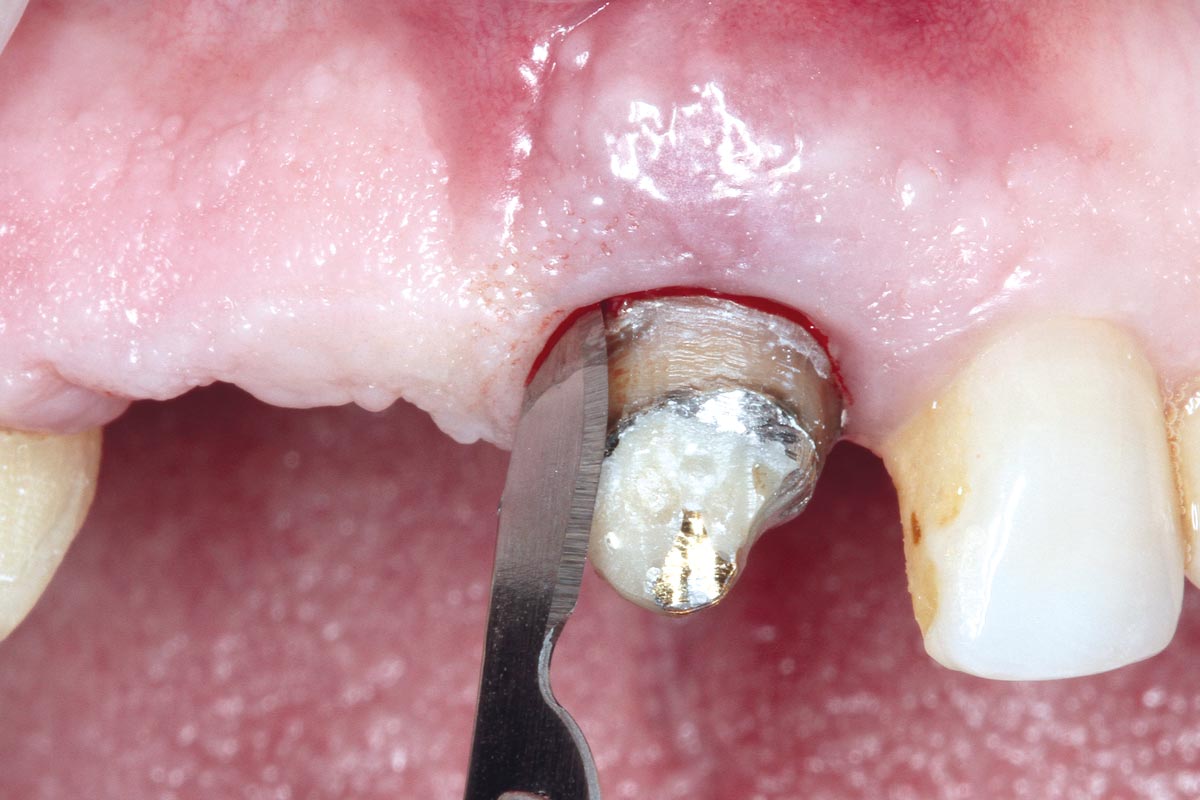

07/17 - cerabone® mixed with Straumann® Emdogain® applied to the extraction socket.

Socket preservation using cerabone® and Straumann® Emdogain® - Dr. S. Pelekanos